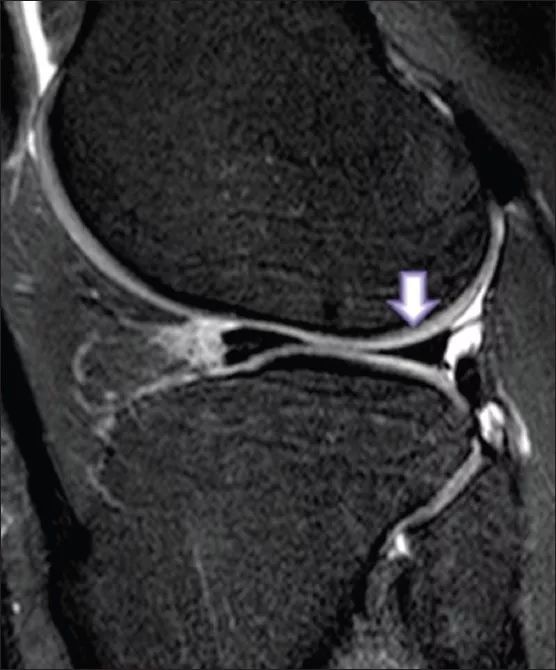

半月板撕裂 醫學影像學習園地